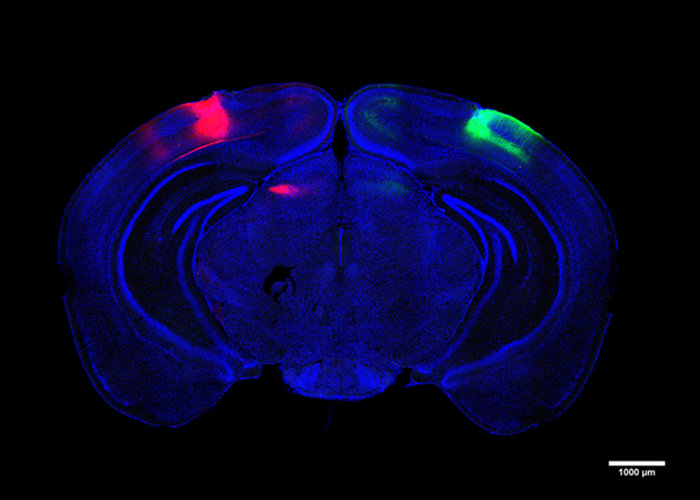

图片:科学家追踪并研究了连接大脑各半球视觉皮质的神经元。

Cross-hemispheric细胞

在这项研究中,Adaikkan, Tsai, Thomas McHugh和合著者发现并追踪了V1神经元,它们的轴突通过胼胝体一直延伸到大脑另一侧的V1细胞,胼胝体连接大脑半球。他们发现,在那里,跨半球(CH)神经元与目标细胞形成连接或突触,为它们提供“兴奋性”刺激来驱动它们的活动。Adaikkan还发现,CH神经元比一般的V1神经元或其他与记忆密切相关的区域(如海马体或前额叶皮层)的神经元更容易被新奇的辨别任务激活。